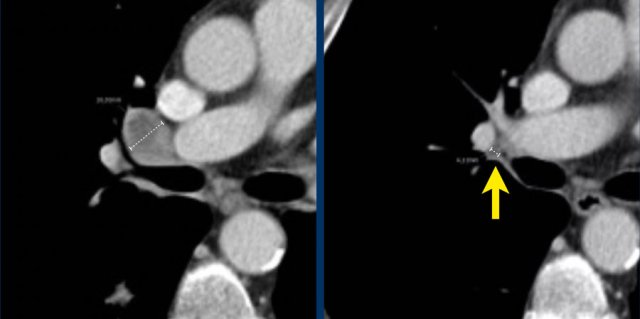

Measurement includes hypervascular rim

When a lesion has a hypervascular rim, this is included in measuring the longest diameter, because it represent viable tumor tissue.

The CT images in the arterial and portovenous phase of a 71-year-old male show liver metastases of a neuro-endocrine tumour of the esophagus.

Note that the hypervascular rim is better appreciated in the arterial phase.

The large hypervascular rim is included in the measurement of the largest diameter.